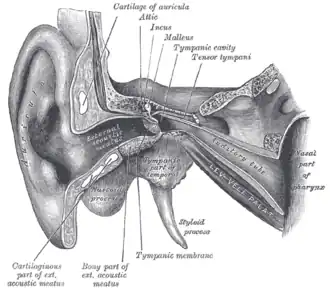

External and middle ear. Eustachian tube labelled as auditory tube. | |

The Eustachian tube (/juːˈsteɪʃən/), also called the auditory tube or pharyngotympanic tube,[1] is a tube that links the nasopharynx to the middle ear, of which it is also a part. In adult humans, the Eustachian tube is approximately 35 mm (1.4 in) long and 3 mm (0.12 in) in diameter.[2] It is named after the sixteenth-century Italian anatomist Bartolomeo Eustachi.[3]

The Eustachian tube extends from the anterior wall of the middle ear to the lateral wall of the nasopharynx, approximately at the level of the inferior nasal concha. It consists of a bony part and a cartilaginous part.

The bony part (1⁄3) nearest to the middle ear is made of bone and is about 12 mm in length. It begins in the anterior wall of the tympanic cavity, below the septum canalis musculotubarius, and, gradually narrowing, ends at the angle of junction of the squamous and the petrous parts of the temporal bone, its extremity presenting a jagged margin which serves for the attachment of the cartilaginous part.[5] The vestibule of the Eustachian tube is known as the protympanum,[6] The protympanum is also known as the anterior part of the bony part of the tube.[7]

The cartilaginous part of the Eustachian tube is about 24 mm in length and is formed of a triangular plate of elastic fibrocartilage, the apex of which is attached to the margin of the medial end of the bony part of the tube, while its base lies directly under the mucous membrane of the nasal part of the pharynx, where it forms an elevation, the torus tubarius or cushion, behind the pharyngeal opening of the auditory tube.

The upper edge of the cartilage is curled upon itself, being bent laterally so as to present on transverse section the appearance of a hook; a groove or furrow is thus produced, which is open below and laterally, and this part of the canal is completed by fibrous membrane. The cartilage lies in a groove between the petrous part of the temporal bone and the great wing of the sphenoid; this groove ends opposite the middle of the medial pterygoid plate. The cartilaginous and bony portions of the tube are not in the same plane, the former inclining downward a little more than the latter. The diameter of the tube is not uniform throughout, being greatest at the pharyngeal opening, least at the junction of the bony and cartilaginous portions, and again increased toward the tympanic cavity; the narrowest part of the tube is termed the isthmus.